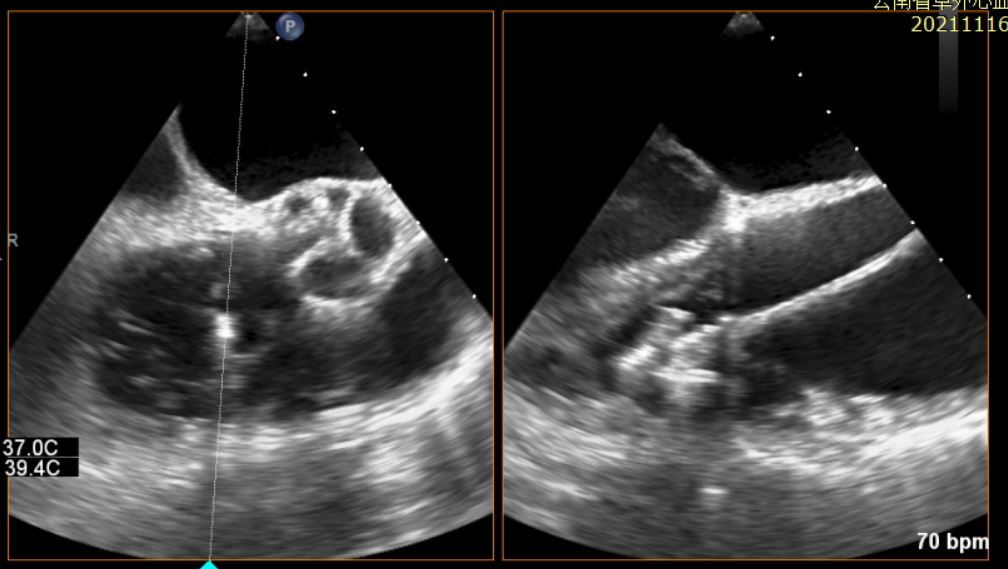

患者为一名77岁高龄的老年女性,罹患极重度三尖瓣反流,临床症状明确,合并高血压,房颤,右心功能不全等多种并发症,经多学科讨论判定为传统外科手术高危患者,经伦理委员会讨论批准,行经导管介入三尖瓣修复技术。术前经胸超声提示极重度三尖瓣反流(图1)。

图1:术前TEE、TEE提示极重度三尖瓣反流。